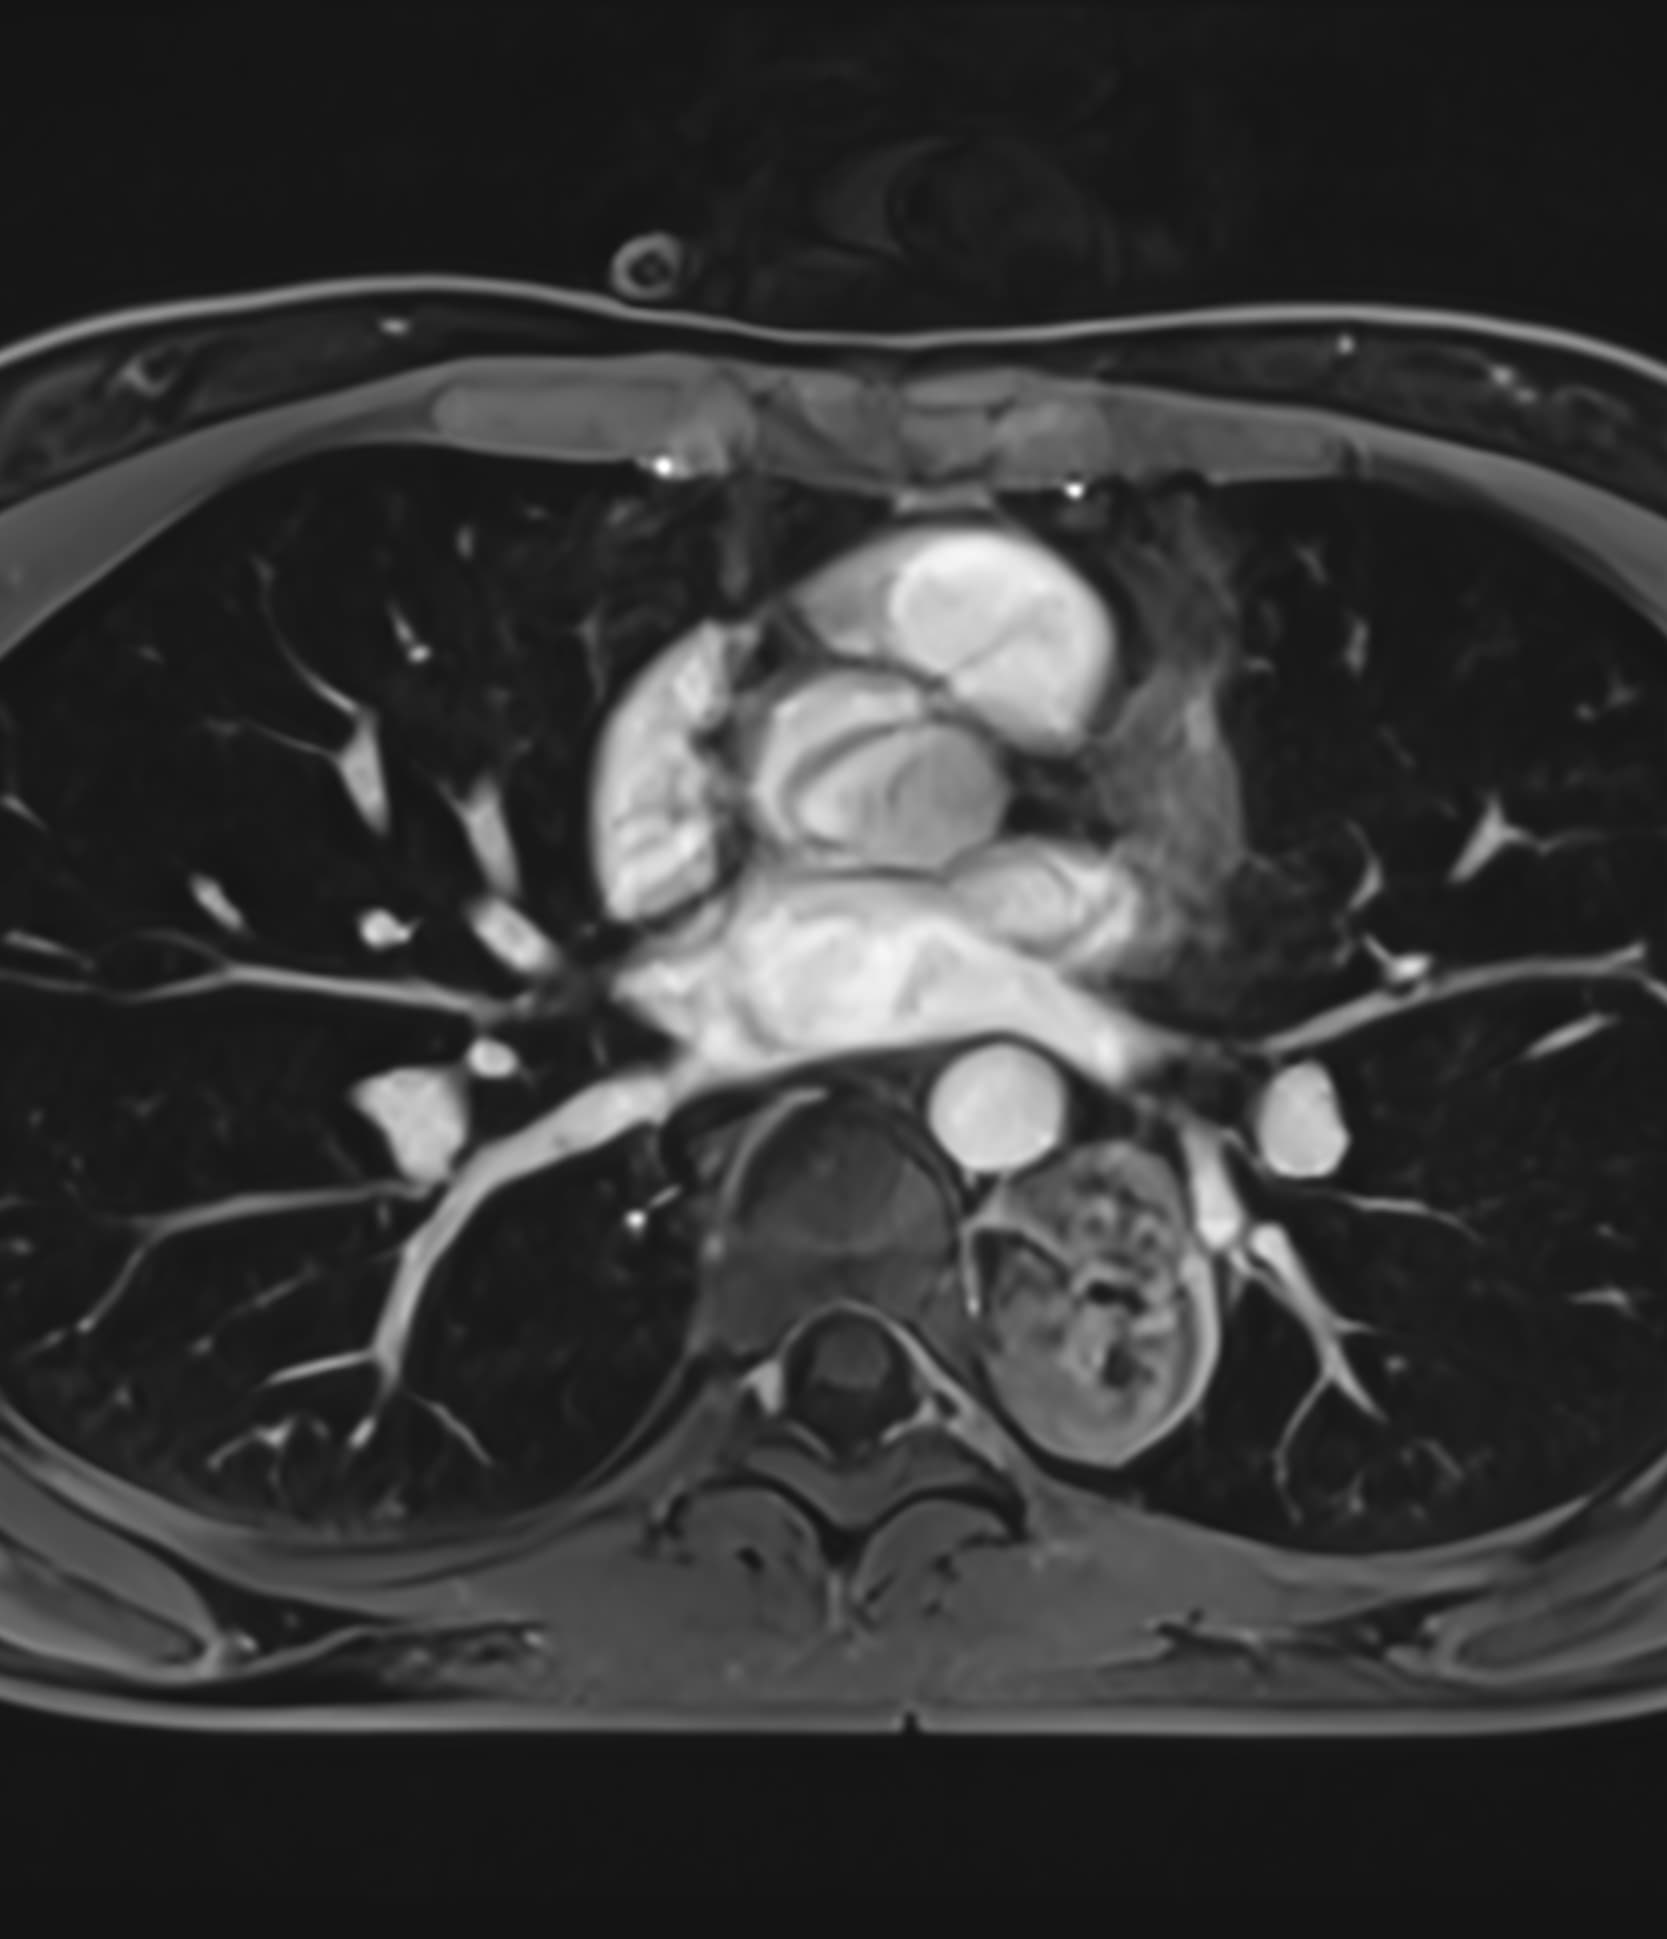

See real-world examples of SwiftMR™ across various MRI systems and anatomical regions

Scan time 03:14

Scan time 02:07

Scan time 03:08

Scan time 1:12

Scan time 04:53

Scan time 1:46